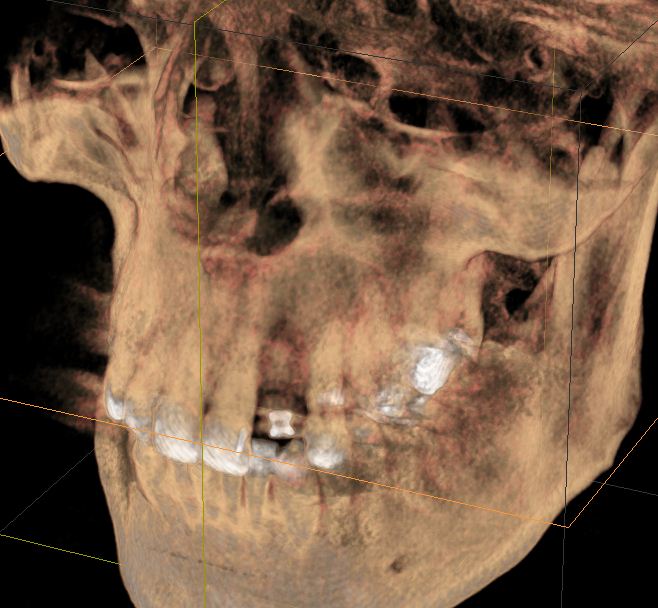

Bei nicht oder nicht vollständig durchgebrochenen Weisheitszähnen wird die darüber liegende Schleimhaut beiseite geschoben und der darüber liegende Knochen entfernt. Dann wird der Zahn mit einem Hebel entfernt. Ist dies aus anatomischen Gründen nicht im Ganzen möglich, wird das Durchtrennen des Zahnes notwendig. Das Trennen des Zahns ist obligat wenn die Platzverhältnisse keine andere Entfernungsmethode zulassen oder sich die Zahnwurzeln in unmittelbarer Nervnähe befinden. Die Wunde kann vernäht oder offen gelassen werden. Um Folgeschäden wie eine Taubheit der Unterlippe zu vermeiden kann präoperativ ein 3D DVT ( DIGITALES VOLUMENTOMOGRAMM ) zur Abklärung der Lagebeziehung von Wurzeln und Nerv sowie zur OP-Planung angefertigt werden.

Zu einer Wurzelspitzen-Entfernung wird Ihr Zahnarzt oder Kieferchirurg dann raten, wenn ein chronisch entzündlicher Prozess durch eine Wurzelbehandlung nicht behoben werden kann oder eine konventionelle Wurzelbehandlung nicht möglich ist. Auch wenn sich im Röntgenbild Veränderungen im Bereich der Wurzelspitze zeigen, die nicht eindeutig zuzuordnen sind, kann eine Wurzelspitzen-Resektion empfehlenswert sein. Um die Region der Wurzelspitzen genauer abzubilden ist es präoperativ möglich, durch ein 3D DVT (DIGITALES VOLUMENTOMOGRAMM) die Region dreidimensional abzubilden, um so eine bessere OP-Planung zu erhalten oder sich über die Frage der Erhaltungswürdigkeit des Zahns klar zu werden.

Solch ein Vorgehen erfordert allerdings auch eine möglichst exakte Diagnostik, die bei uns in der Regel dreidimensional mittels DVT erfolgt. So kann die Implantation vorher am Rechner dreidimensional simuliert werden, bevor sie am Patienten durchgeführt wird.